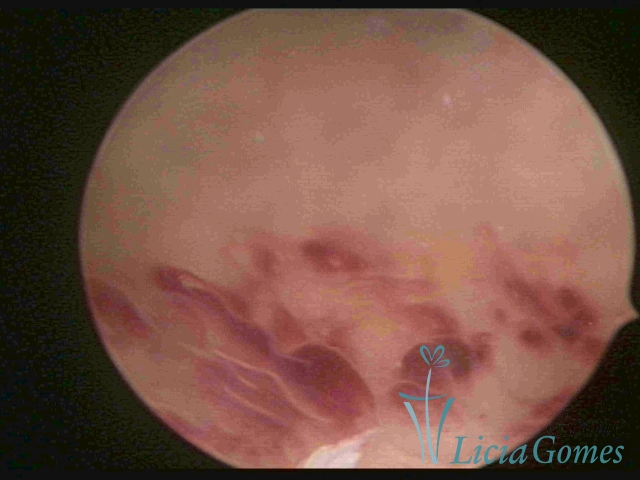

CHRONIC ENDOMETRITIS

The surface of the endometrium may present changes such as a red punctuate forming vascular balls, a smooth, hypervascularized endometrium or intensely presenting red areas, with accurate edges and yellowish white spots in its interior, providing a "STRAWBERRY PEEL" aspect, a pale yellow color of fundic and lateral commissures, in contrast with the intense red color present in the walls.

On Advanced chronic endometritis, a thin endometrium is observed, presenting denude, sometimes ulcered areas of a greenish gray color with micro varicosities presenting a hazel color, more accentuated in the cornual regions (vascular dystrophy.)